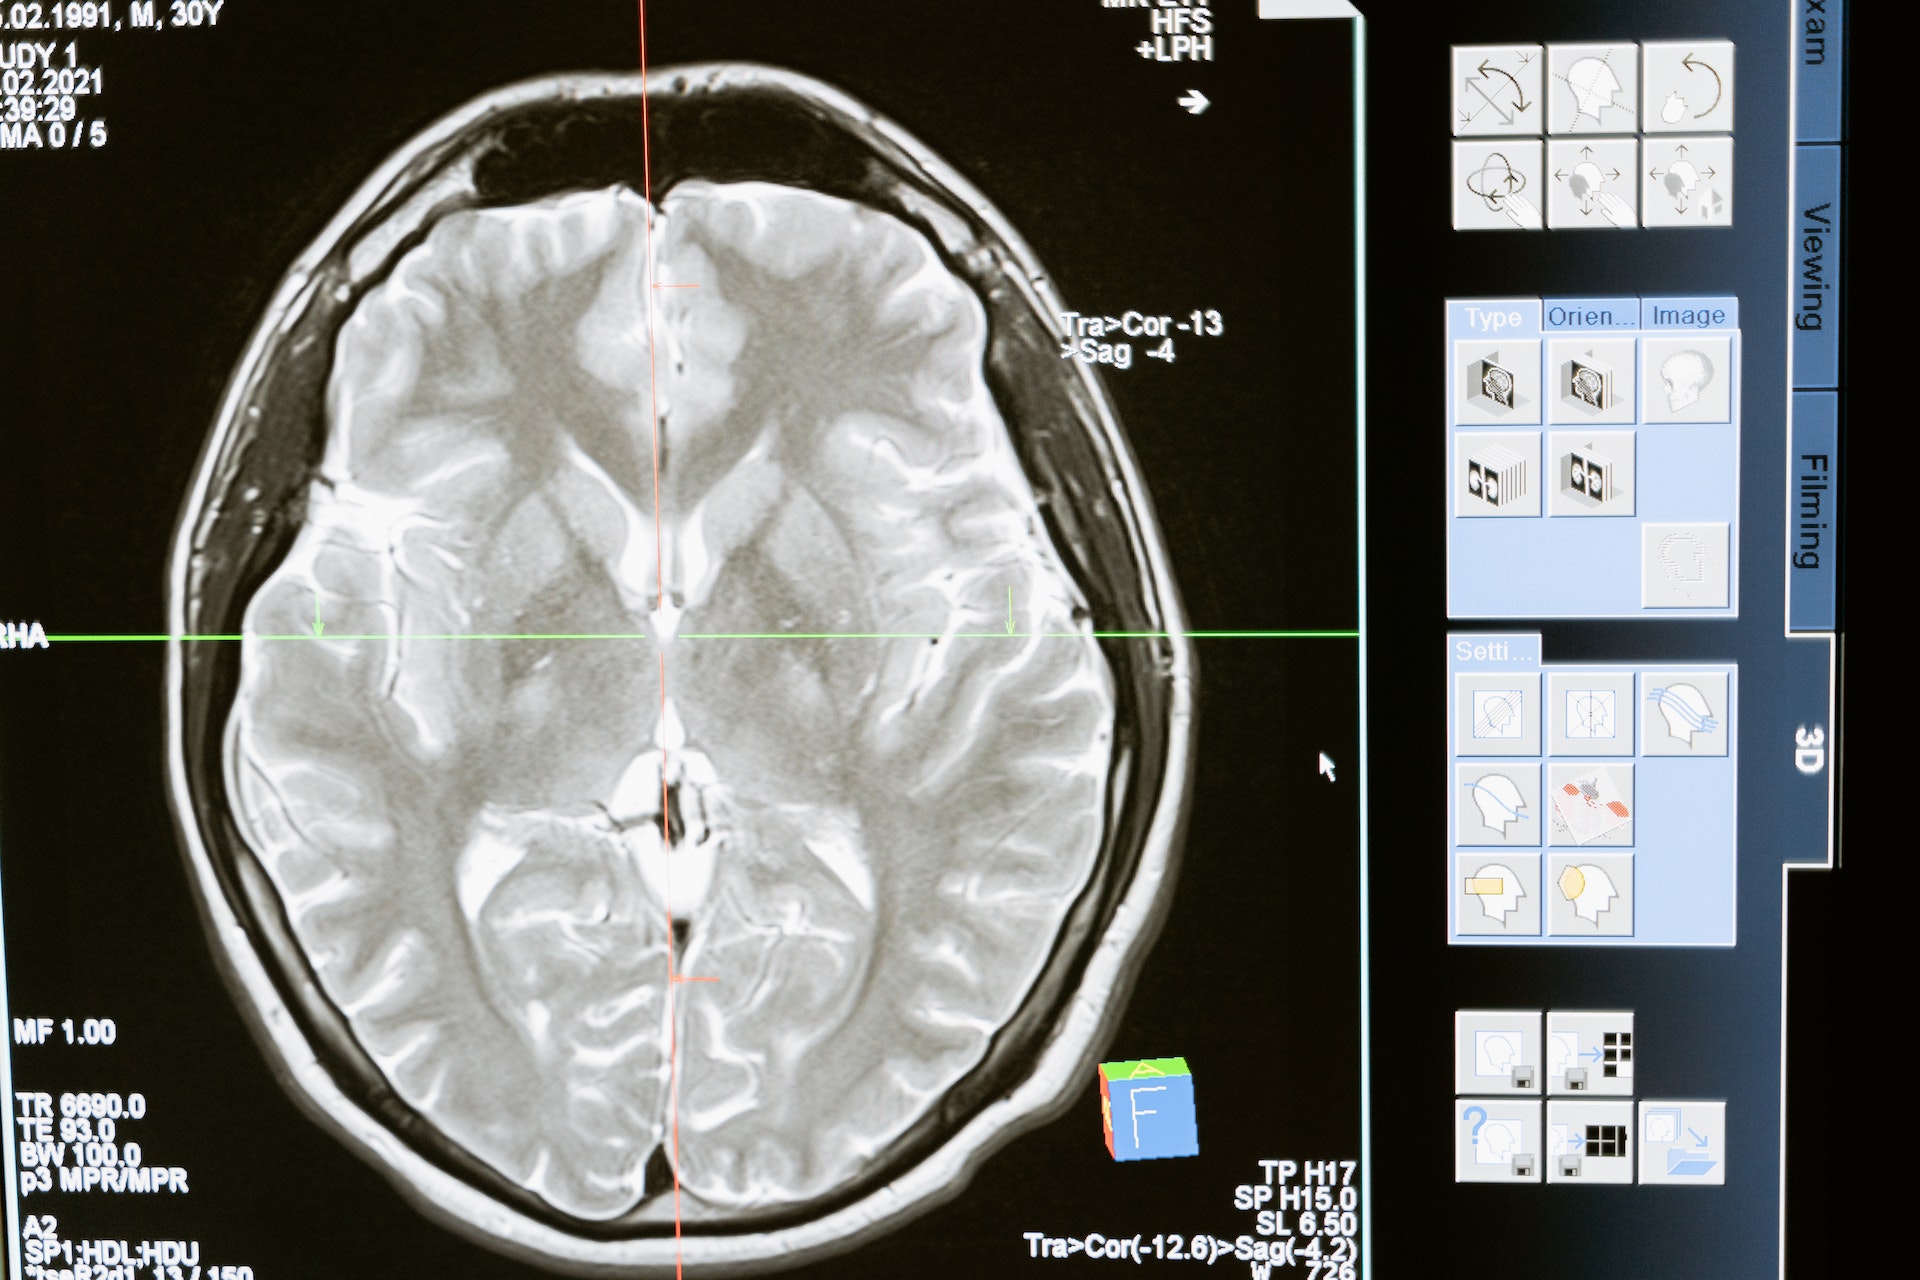

MRI Brain © MART PRODUCTION on Pexel

One of the known consequences of Alzheimer’s disease is the formation of Zn-rich plaques in the brain: amyloid plaques. In this study, the researchers worked on mouse models genetically modified to develop this type of plaque after a period of 9 months. The researchers demonstrated that the presence of plaques altered the isotopic composition of the mice’s brains, which became richer in heavy Zn isotopes. This is explained by a change in the speciation of Zn, linked in the plaque proteins to amino acids enriched in heavy Zn isotopes (histidine and glutamate). As a result, it is possible to monitor the evolution of the disease by measuring the isotopic composition of Zn.